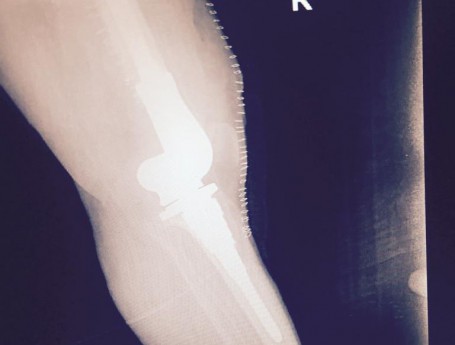

Total Knee Arthroplasty After a non-union